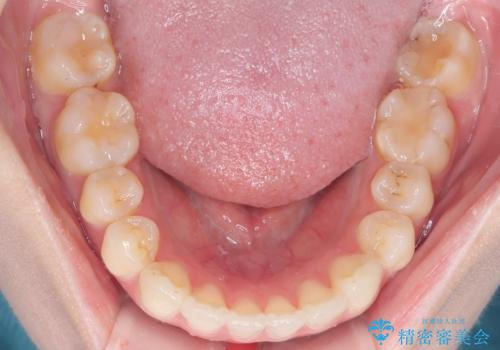

審美ワイヤー矯正とTAD併用による犬歯の遠心移動

- 歯並びの乱れを改善したいと来院されました。精密検査の結果、犬歯を奥へ動かすことで、より美しい口元と安定した咬み合わせが得られると診断。患者様のご希望から、目立ちにくい審美ワイヤー矯正を採用し、効率的な歯の移動のために**リンガルアーチとTAD(矯正用アンカースクリュー)**を併用する計画を立てました。これにより、抜歯せずにスペースを確保し、犬歯をスムーズに遠心へ移動させます。

今回の矯正では、装置が目立たないよう透明なブラケットと白いワイヤーを使用。さらに、効率的な歯の移動のために、歯の裏側にリンガルアーチを設置しました。また、確実な奥歯の移動のために**TAD(矯正用アンカースクリュー)**を一時的に使用。これにより、犬歯を狙った位置へ正確に動かすことが可能に。目立ちにくい装置で快適に過ごしながら、理想的な歯並びと咬み合わせを獲得していただけました。